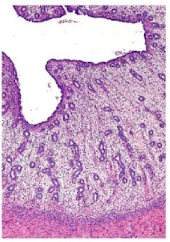

What organ is in the image provided and what phase of the estrous cycle is it in?

uterus in proestrus